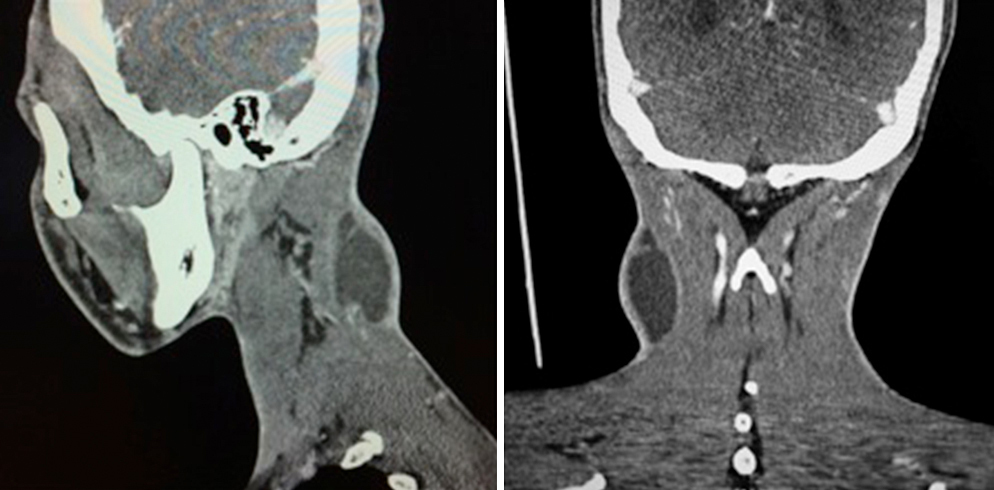

Quel est votre diagnostic ?

Il s'agit de l’image TDM d’une adénopathie cervicale haute latéralisée à droite, nécrotique, à parois épaissies révélant une tuberculose ganglionnaire chez un patient de 26 ans. Les mycobactéries en cause dans les adénopathies d’origine infectieuse sont le plus souvent Mycobacterium tuberculosis. Les adénopathies sont le plus souvent unilatérales, volumineuses, peu inflammatoires et évoluent parfois vers une fistulisation cutanée. Le diagnostic peut être aiguillé par l’imagerie, mais repose avant tout sur une ponction­biopsie de l’adénopathie avec examen direct et culture, voire PCR. L’intradermoréaction tuberculinique ou la détection de la production d’interféron gamma peuvent également être utiles. Il faut penser à chercher d’autres localisations tuberculeuses ainsi qu’une immunodépression sous­jacente. Le traitement repose sur une quadrithérapie antituberculeuse prolongée. Lorsque ce sont des mycobactéries atypiques, il s’agit d’infections à Mycobacterium avium ou scrofulaceum. Le scanner est aujourd’hui très souvent réalisé en première intention du fait de son accessibilité, de sa grande reproductibilité et d’une exploration complète ; il est néanmoins plus coûteux que l’échographie et nécessite une injection de produit de contraste ; son principal intérêt réside dans l’exploration des chaînes ganglionnaires profondes.